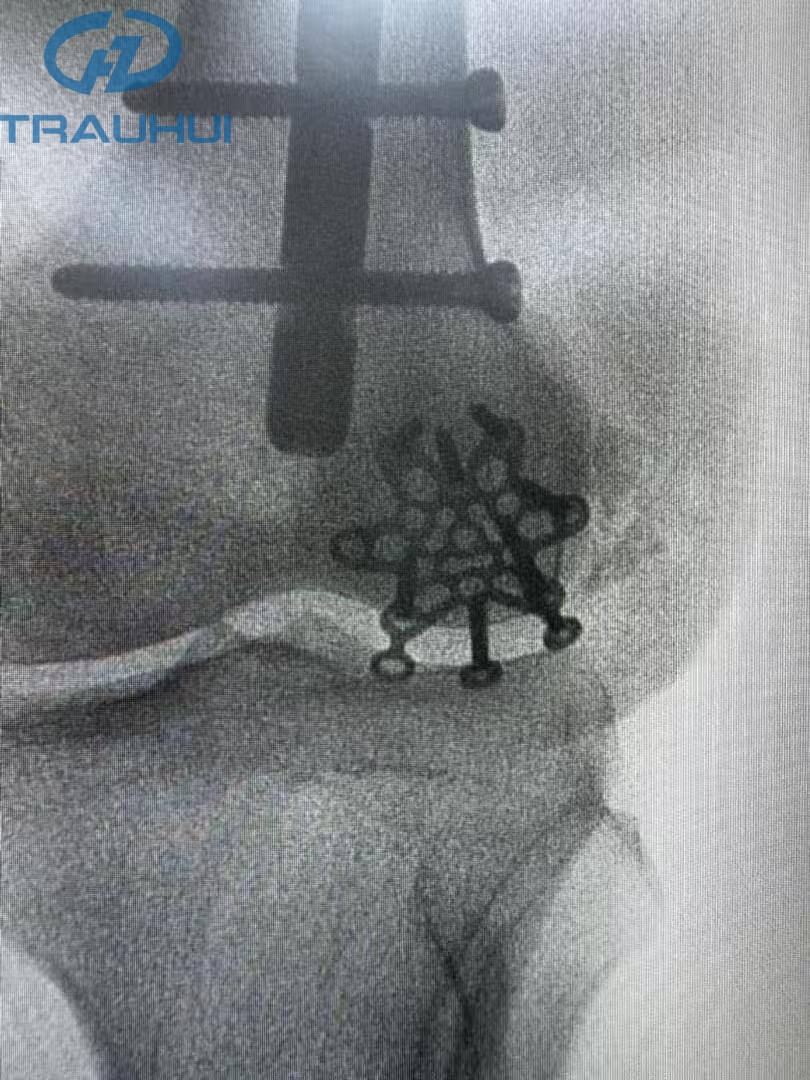

Anterior Patella Plates2.jpg

Figure 3: X-Ray

The post-surgery X-ray confirmed what the surgeon felt in the OR: unmatched stability. By replacing the "settling" nature of cerclage wires with the rigid, anatomical fixation of our new plate, the patient is now positioned for a faster rehabilitation with a reduced risk of hardware failure.